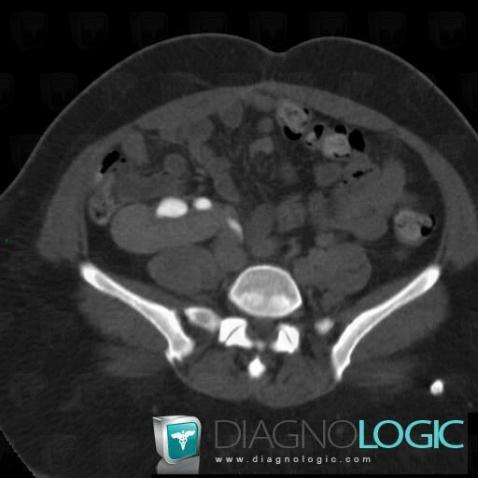

Duplication-voies excrétrices, Uretère, Scanner

- Diagnostic Duplication des voies excrétrices, Localisation(s) Uretère, comportant les gammes